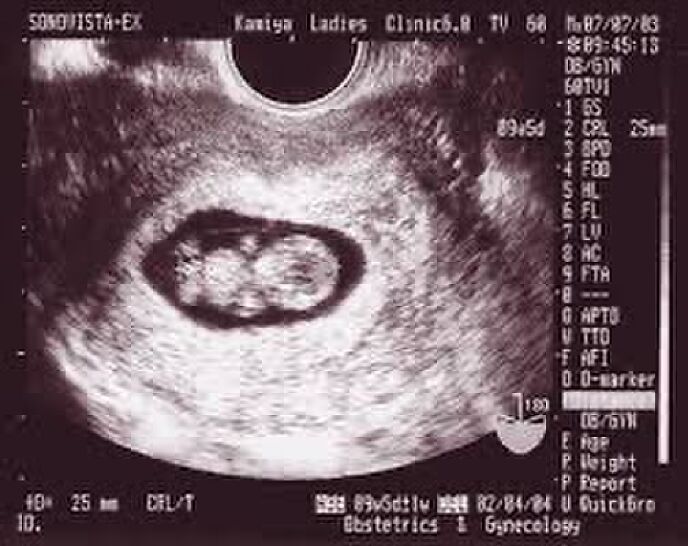

その機械のコードの先にモニターが付いていた。そのモニターには白黒の物が映っていて先生が機械を動かしている。先生の手が止まり映し出された映像に私はゴクリと息をのんだ、、、。

小さな頭と胴体、手足。ハッキリとそれは映っていた。

小さな手足がピクピクと動いていて、胴体の右上の辺りに鼓動があった。

小さな体で懸命に生きようとしている。

先生によると現在妊娠16週と2日で出産予定は12月ということだった。

16週に入った赤ちゃんは胎児と言われ

人間として扱われる、中絶が選択肢としてあるのは15週までとのことだった。